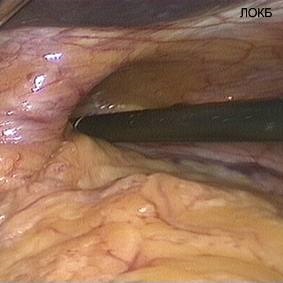

Cel mai recunoscut astăzi baza pentru punerea în aplicare a chirurgiei antireflux este dezvoltarea simptomelor de GERD la pacientii cu hernie hiatala (hernie hiatală, fig. 1, 2).

Figurile 1 și 2. hernie hiatală - cauza bolii de reflux gastro-esofagian (foto intraoperator)

Schimbarea relațiilor anatomice naturale în zona de tranziție gastroesofagian se referă la cele mai frecvente cauze ale unei defecțiuni mecanice a sfincterului esofagian inferior. Boala cauza organica predetermină un impact redus asupra eficienței chimioterapeutic diferitelor sale simptome. Pe de altă parte, manifestările minime de reflux gastro-esofagian, care apare pe fondul unei hernie hiatala, în multe cazuri, modificări simple, care pot fi supuse la modul de corectare sau terapia standard. Astfel, o abordare echilibrată la determinarea indicațiilor pentru tratamentul chirurgical al GERD, condiționate (sau agravare) hiatala hernie, trebuie să țină seama de gravitatea manifestărilor clinice ale bolii de reflux gastroesofagian și complicațiile sale. Motivul pentru efectuarea reconstrucției este esofagian antireflux rezistență (sau vnepischevodnyh) manifestări ale bolii la tratamentul medicamentos. efectul acut al tratamentului conservator, nevoia de utilizare continuă a medicamentelor antisecretorii, și în special apariția complicațiilor, sunt în prezent considerate ca indicii obiective pentru o intervenție chirurgicală.